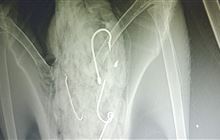

Rare albatross makes remarkable recovery after swallowing multiple fishing hooks

Date: 04 November 2025

Source: Department of Conservation and American Bird Conservancy

A Salvin’s albatross has returned to the wild after successfully recovering from life-saving surgery.